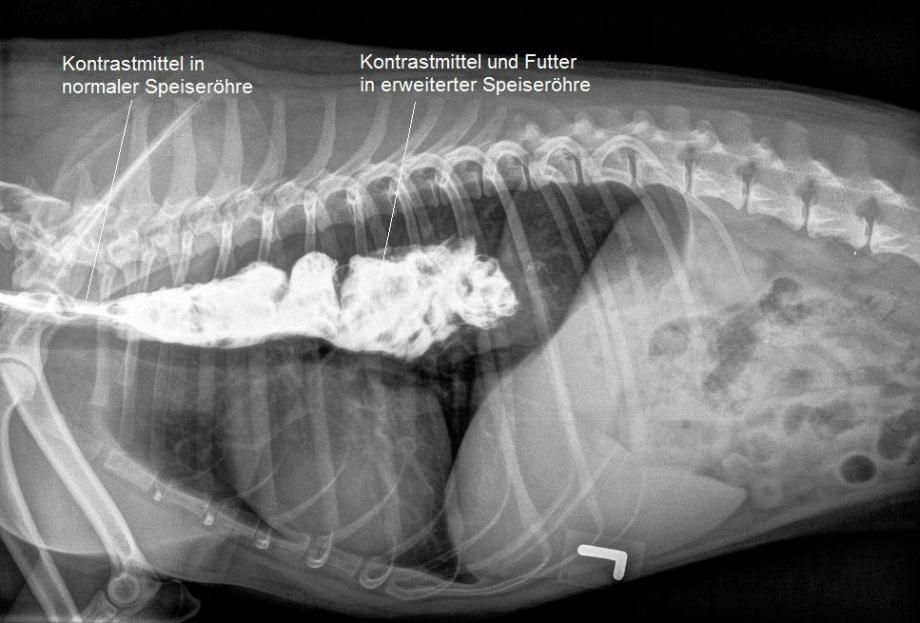

Kontraströntgen

Das Bruströngen ist verdächtig für eine Erweiterung der Speiseröhre in diesem Bereich. Zur weiteren Abklärung erhält Jago nun Futter, welches mit einem Röntgenkontrastmittel vermischt ist. In einer weiteren Röntgenaufnahme wird dann dokumentiert, dass das geschluckte Futter nicht ordnungsgemäss im Magen gelandet ist, sondern in der stark erweiterten Speiseröhre in der Brusthöhle liegen geblieben ist - der Hund leidet unter einem Megaösophagus.